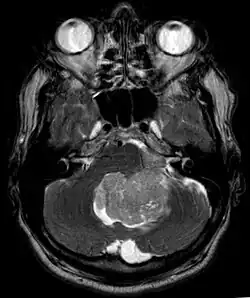

Ependymoma of 4.ventricle in MRI. -

Ependymoma of 4.ventricle in MRI. Left without, right with contrast-enhancement.

An ependymoma is a tumor that arises from the ependyma, a tissue of the central nervous system. Usually, in pediatric cases the location is intracranial, while in adults it is spinal. The common location of intracranial ependymomas is the floor of the fourth ventricle. Rarely, ependymomas can occur in the pelvic cavity.

Ependymomas make up about 5% of adult intracranial gliomas and up to 10% of childhood tumors of the central nervous system (CNS). Their occurrence seems to peak at age 5 years and then again at age 35. They develop from cells that line both the hollow cavities of the brain and the central canal containing the spinal cord, but they usually arise from the floor of the fourth ventricle, situated in the lower back portion of the brain, where they may produce headache, nausea and vomiting by obstructing the flow of cerebrospinal fluid. This obstruction may also cause hydrocephalus. They may also arise in the spinal cord, conus medullaris and supratentorial locations.[7] Other symptoms can include (but are not limited to): loss of appetite, difficulty sleeping, temporary inability to distinguish colors, uncontrollable twitching, seeing vertical or horizontal lines when in bright light, and temporary memory loss. It should be remembered that these symptoms also are prevalent in many other illnesses not associated with ependymoma.

Intracranial ependymomas, including supratentorial and posterior fossa, make up 90% of ependymomas in children. The supratentorial region is the upper brain region, or cerebrum, and contains the lateral and third ventricles. The posterior fossa, or infratentorial, is behind or below this region in the area of the brainstem and cerebellum and contains the fourth ventricle. A majority of intracranial pediatric ependymomas are in the posterior fossa.[15] Patients with intracranial ependymomas typically present with increased intracranial pressure that results in headaches, dizziness, nausea, and vomiting. The third location of ependymomas is within the central canal of the spinal cord. Spinal ependymomas comprise about 65% of adult ependymomas and most often occur in the lumbosacral region.[13] Patients with spinal ependymomas can present with back pain, numbness or weakness in the limbs, and urinary or bowel problems.